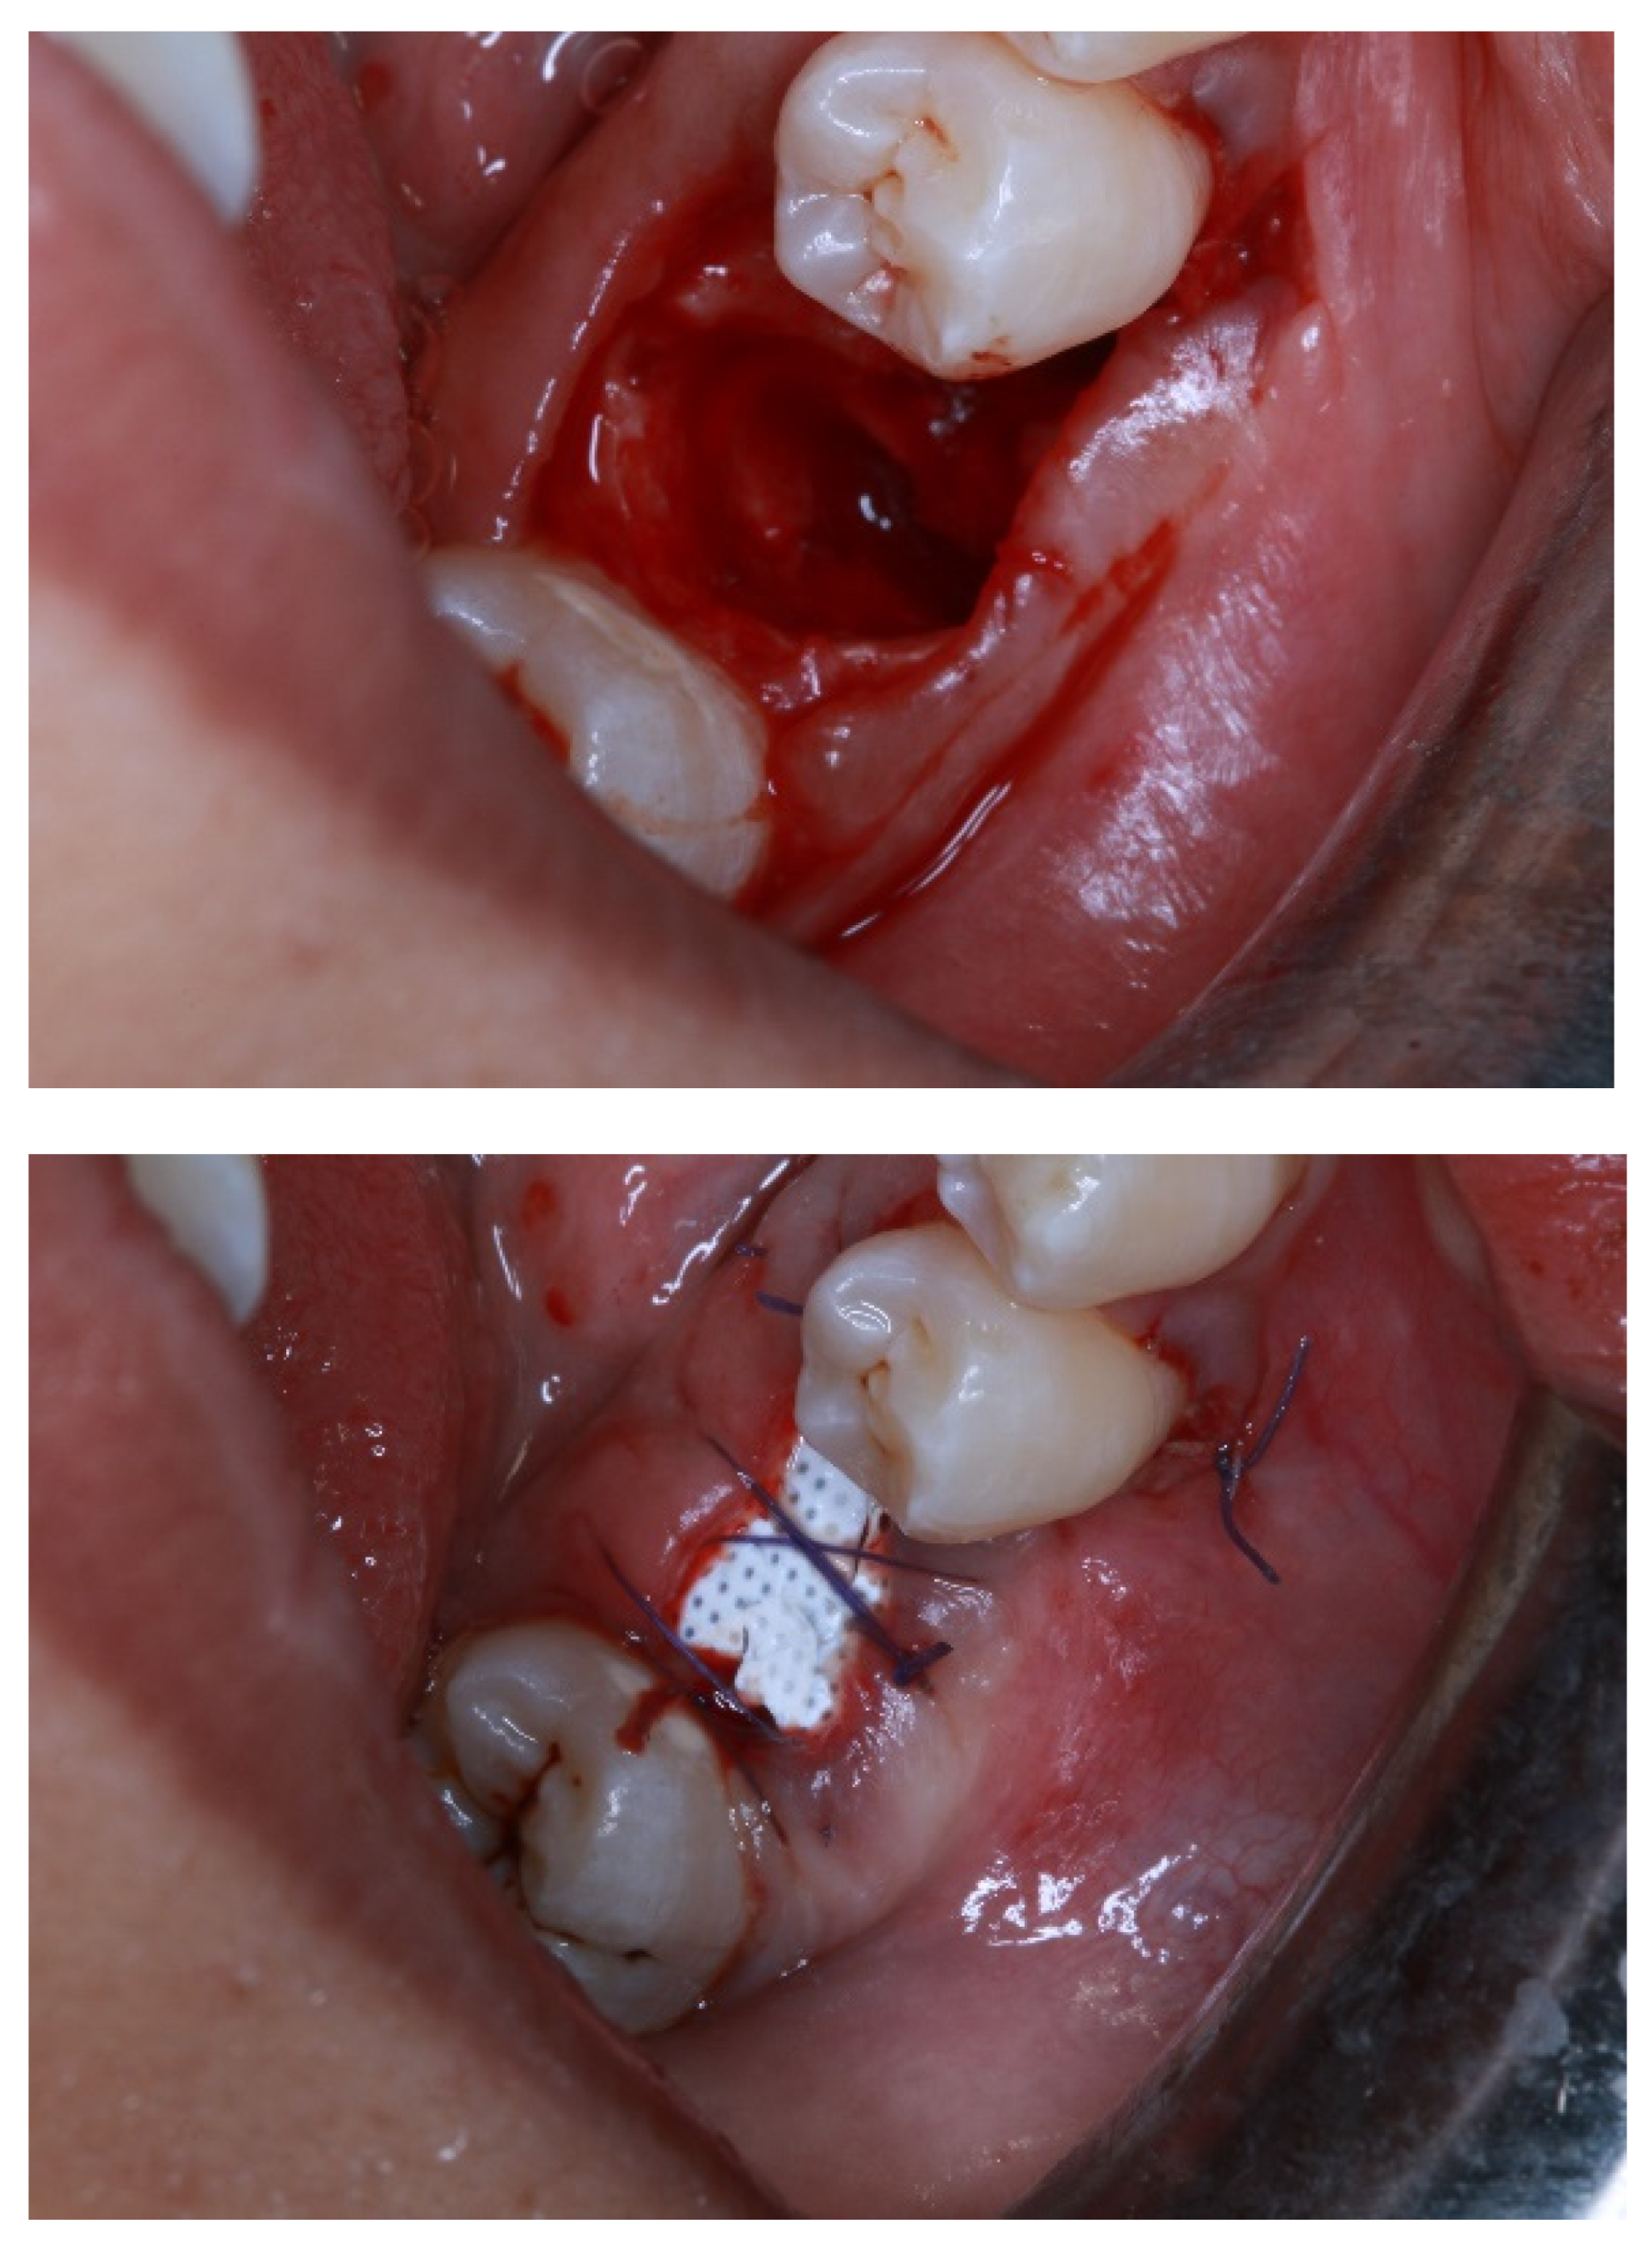

- Alauddin, M.S.; Ramli, H. Management of Membrane Exposure Utilizing Concentrated Growth Factor (CFG) in Guided Bone Regeneration: A Clinical Report. Open Dent. J. 2020, 14, 763–768. [Google Scholar] [CrossRef]